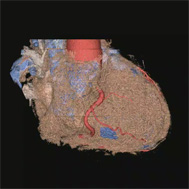

CT画像を用いた3次元画像は今でこそ多くの施設で活用されるようになりましたが、その開発に当放射線科は深く関ってきました。現在では、大動脈瘤や大動脈解離などの大血管疾患や閉塞性動脈硬化症などの末梢血管疾患に加え心臓の冠動脈の3次元画像も提供できるようになり、これまで血管造影でしか得られなかった情報をおよそ10分程度の外来検査で正確に知ることができるようになりました。また、早期脳梗塞の診断において注目されているCT perfusion(CT灌流画像)も海外の大学と共同で開発し国内外での普及に努めてきました。これらの成果は欧州放射線学会から金賞ならびに銀賞を授与され、また日本医学放射線学会でも金賞を受賞し、広く国内外で認められています。

仮想血管内視鏡